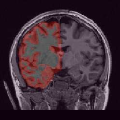

In order to evaluate the impact of such smoothing, classification tests have been conducted based on images reconstructed with both methods. Gray and white matter classification results using the Morphologist 2012 pipeline of -MRI toolbox of Brainvisa software444http://brainvisa.info at and are compared to those obtained without acceleration (i.e. at ), considered as the ground truth. Displayed results in Fig. 2 show that classification errors occur due to reconstruction artifacts for mSENSE, especially at . Results show that the gray matter is better classified using our 3D-UWR-SENSE algorithm especially next to the artifact into the red circle (Fig. 2 []), which lies at the frontier between the white and gray matters. Moreover, reconstruction noise with mSENSE in the centre of the white matter (left red circle in Fig 2 []) also causes miss-classification errors far from the gray/while matter frontier. However, at and classification performance is rather similar for both methods, which confirms the ability of the proposed method to attenuate reconstruction artifacts while keeping classification results unbiased.